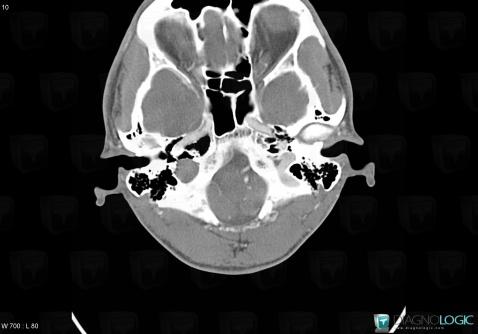

Schwannome, Os temporal, Scanner

Voici les informations spécifiques à l'image clé ci dessus:

- Diagnostic Schwannome, Localisation(s) Os temporal, comportant les gammes Lésions de l'apex pétreuse, Ostéolyse de l'oreille moyenne ou de la mastoide